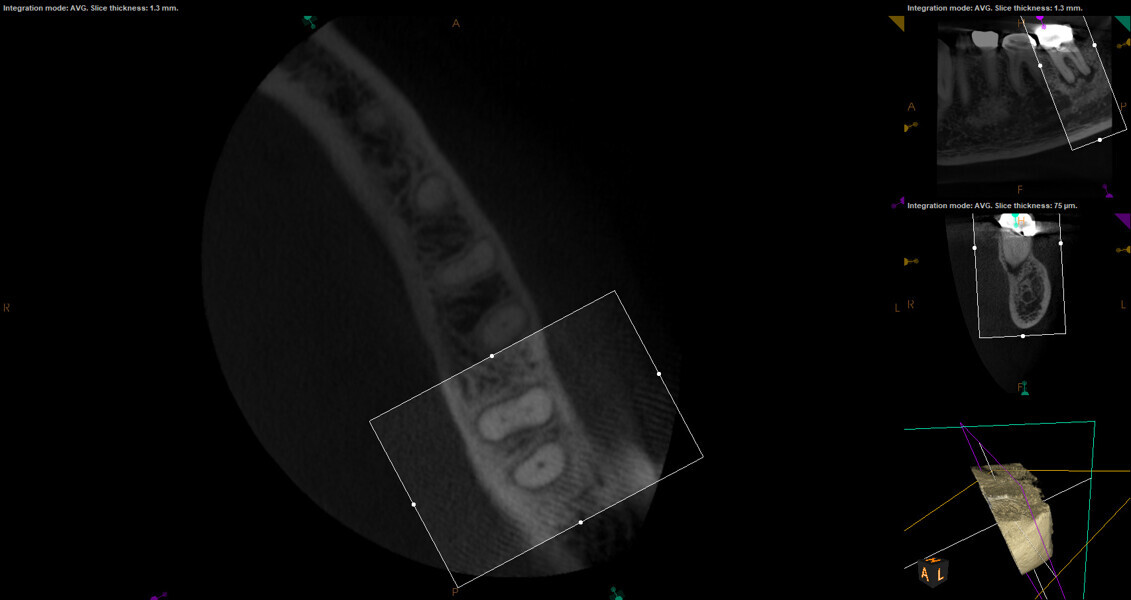

Fig. 17a: Case assisted with CBCT to determine anatomy pre-operatively. Note the multiple cross sections moving apically and the correlation to the 2-D view. Note also the conservative taper in relation to the root width. (Courtesy of Dr. Brett Gilbert)

Fig. 17b: Case assisted with CBCT to determine anatomy pre-operatively. Note the multiple cross sections moving apically and the correlation to the 2-D view. Note also the conservative taper in relation to the root width. (Courtesy of Dr. Brett Gilbert)

Fig. 17c: Case assisted with CBCT to determine anatomy pre-operatively. Note the multiple cross sections moving apically and the correlation to the 2-D view. Note also the conservative taper in relation to the root width. (Courtesy of Dr. Brett Gilbert)

Fig. 17d: Case assisted with CBCT to determine anatomy pre-operatively. Note the multiple cross sections moving apically and the correlation to the 2-D view. Note also the conservative taper in relation to the root width. (Courtesy of Dr. Brett Gilbert)

Fig. 17e: Case assisted with CBCT to determine anatomy pre-operatively. Note the multiple cross sections moving apically and the correlation to the 2-D view. Note also the conservative taper in relation to the root width. (Courtesy of Dr. Brett Gilbert)

Fig. 17f: Case assisted with CBCT to determine anatomy pre-operatively. Note the multiple cross sections moving apically and the correlation to the 2-D view. Note also the conservative taper in relation to the root width. (Courtesy of Dr. Brett Gilbert)